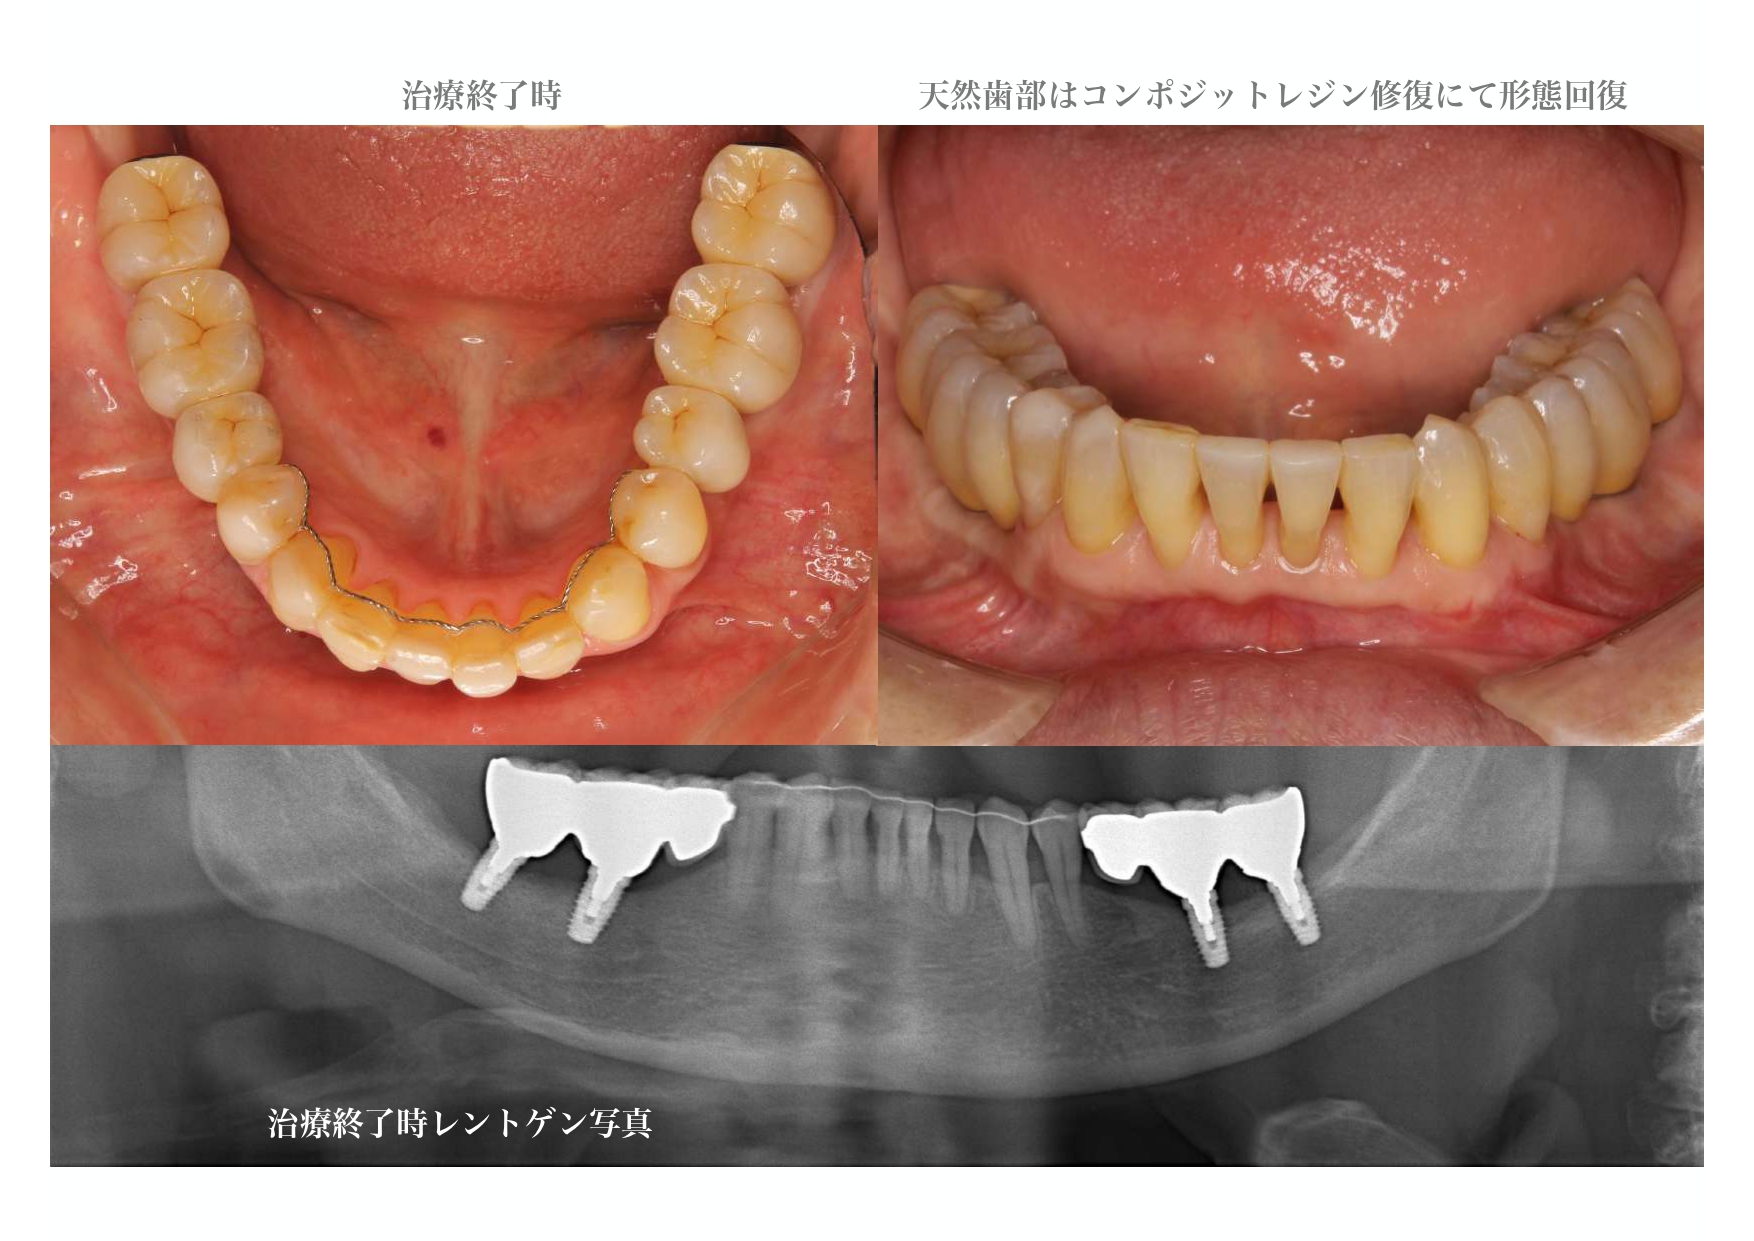

| 治療内容 | 精密検査、コンサルテーション、歯周初期治療、治療用義歯、インプラント4本、GBR、2次手術時歯肉移植、仮歯、部分矯正、上部構造6本、自費コンポジットレジン修復、保定 |

治療詳細